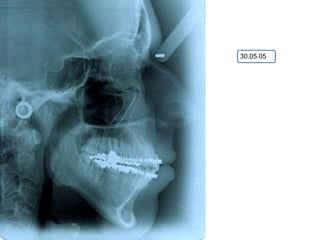

O documento apresenta registros odontológicos de um paciente ao longo de vários anos, incluindo panorâmicas iniciais e subsequentes, remodelações de arcadas dentárias superiores e inferiores ao longo de 7 meses, vedamentos labiais e registros de máxima intercuspidação e guias caninas nas datas listadas.